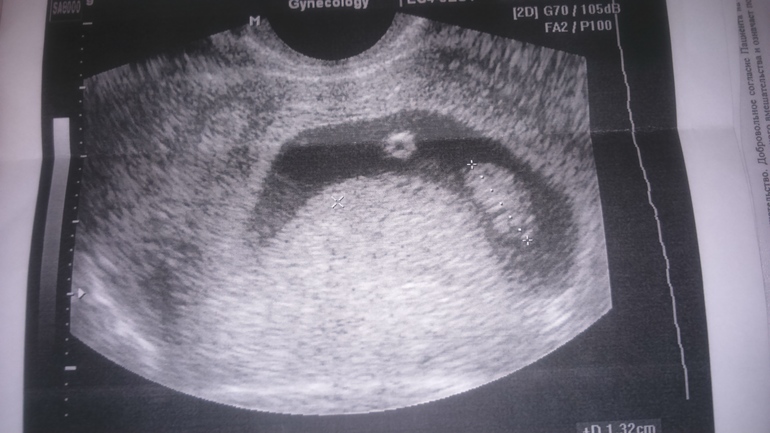

Счастливое узи!!))

Результаты: УЗИ, КТГ, доплера, скринингаСегодня сходила на узи платно. Все отлично, сердечко бъется, ребеночек развивается, соответствует 7 неделям...даже дали послушать как стучит!!)) Теперь я спокойна и счастлива! Всем советую не ждать пока ваш Г решит что пора, моя дак все тянет и тянет, а самим идти, это так успокаивает и поднимает настроение, слов нет!)